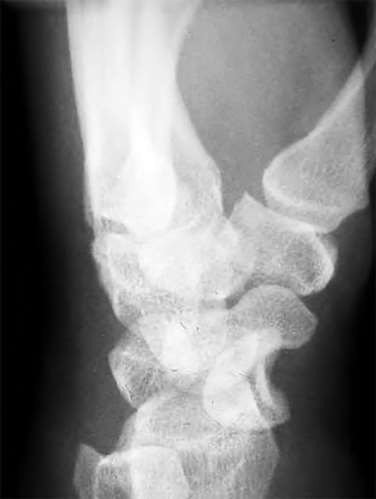

A 35-year-old woman reports wrist pain after a fall onto an outstretched hand. On exam, she has focal tenderness over the wrist snuffbox. A radiograph and CT image are shown in Figures A and B. What is the proper treatment of her injury?